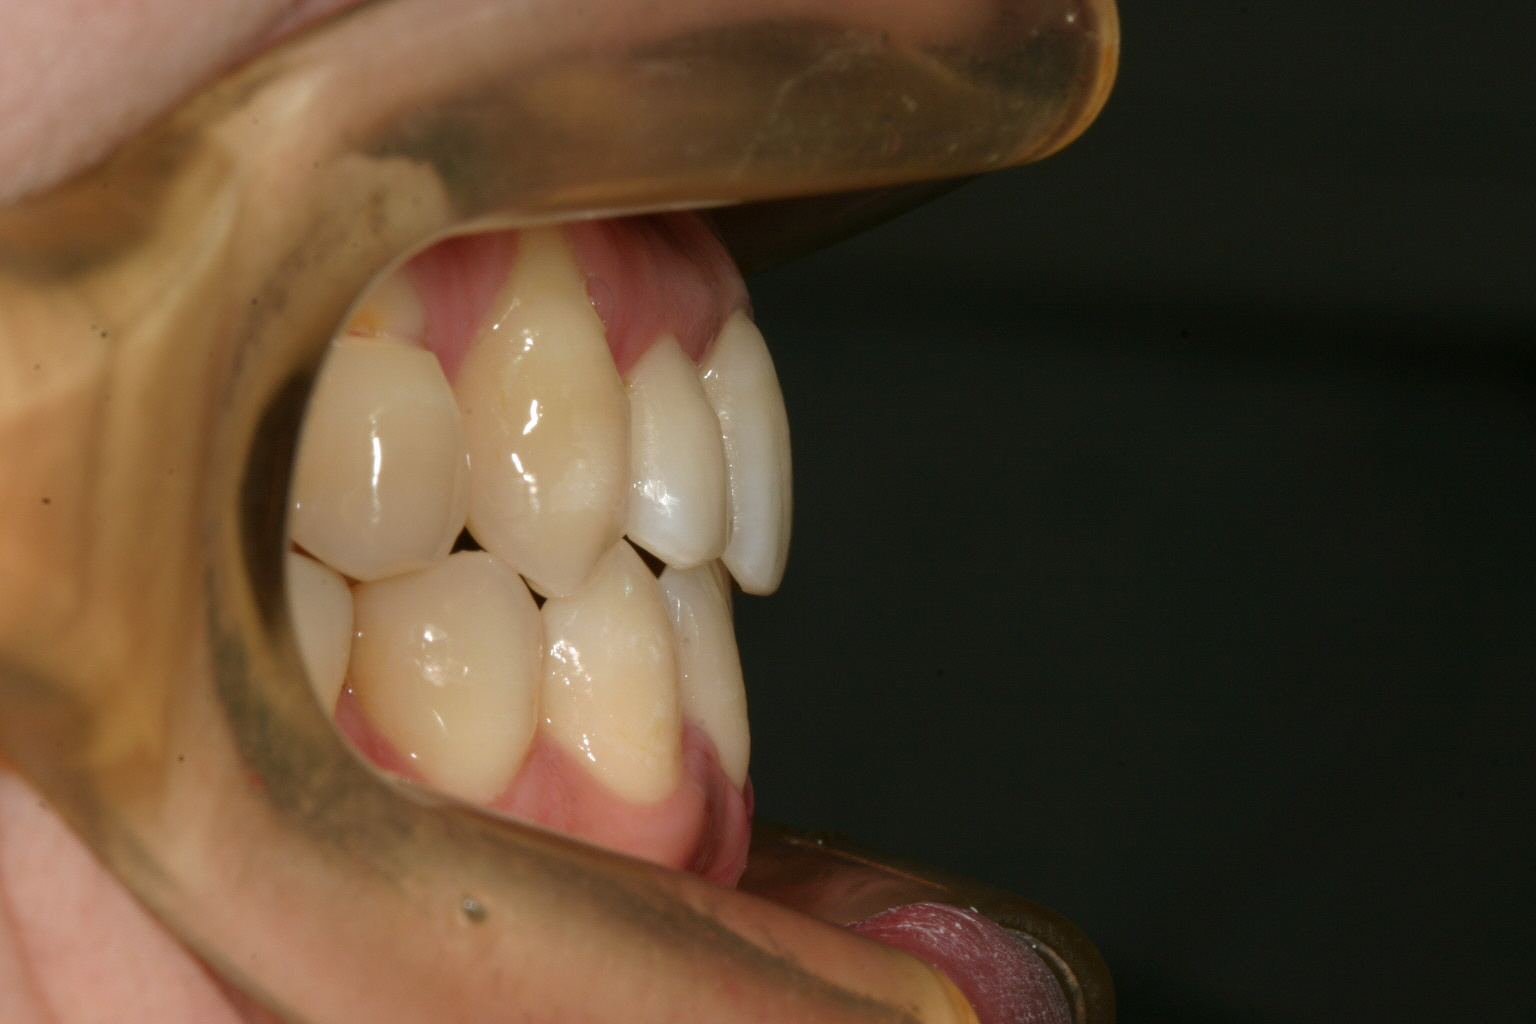

上下叢生の為横から見てもガタガタしてます。

側面観も申し分ないです。